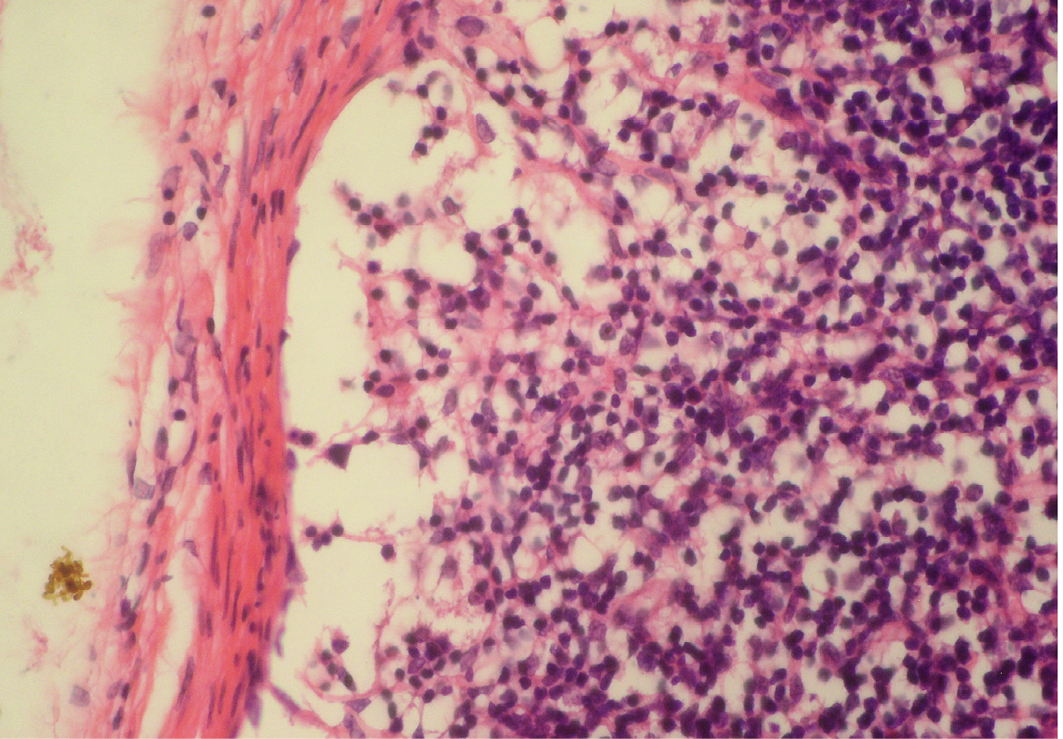

Depletion of follicles in cortex

Thinning of cortex and widened subcapsular space, fibrin threads are also visible; H&E x400